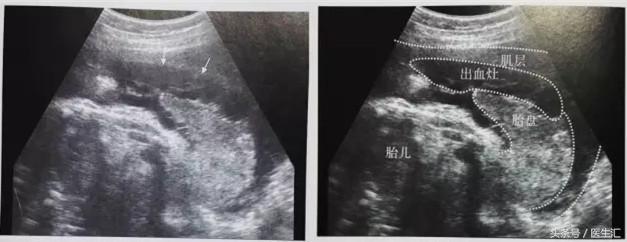

1.胎盘剥离早期:胎盘与子宫壁间见边缘粗糙、形态不规则的液性暗区,其内可见散在斑点状高回声、不均质低回声或杂乱回声,有时为条带状回声(见图6黄色圈内)。有时胎盘后无明显血肿声像,仅有胎盘异常增厚(注意对比历史报告),呈不均增强回声。

(图6)

3.胎盘边缘血窦破裂:胎盘边缘胎膜与宫壁分离、隆起,胎膜下见不均质低回声。(见图7)

(图7)